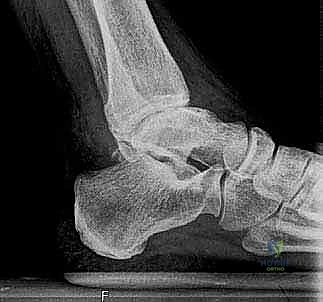

لفهم أهمية جراحة استبدال الكاحل، يجب أولاً فهم تشريح هذا المفصل المعقد. يتكون مفصل الكاحل من التقاء ثلاث عظام رئيسية:

1. عظمة الظنبوب (Tibia): وهي عظمة الساق الكبرى التي تشمل الجزء الداخلي والعلوي من الكاحل.

2. عظمة الشظية (Fibula): وهي عظمة الساق الصغرى التي تشكل الجزء الخارجي من الكاحل.

3. عظمة الكاحل (Talus): وهي العظمة السفلية التي ترتكز عليها عظام الساق وتعمل كمفصلة للحركة.

تُغطى نهايات هذه العظام بطبقة ناعمة ومرنة تسمى الغضروف المفصلي، والذي يعمل كوسادة لامتصاص الصدمات وتقليل الاحتكاك أثناء الحركة. عندما يتآكل هذا الغضروف، تبدأ العظام بالاحتكاك ببعضها البعض، مما يسبب ألماً مبرحاً وتورماً وتيبساً.

2. الفصال العظمي (Osteoarthritis)

يُعرف أيضاً بخشونة المفاصل أو التآكل التدريجي. يحدث نتيجة التقدم في العمر والاستهلاك المستمر للمفصل بمرور الزمن. على عكس مفصل الركبة أو الورك، يعتبر الفصال العظمي الأولي في الكاحل أقل شيوعاً، وعادة ما يكون مرتبطاً بعوامل أخرى.

- تشوه شكل الكاحل: انحراف في شكل القدم أو الكاحل نتيجة انهيار العظام أو تآكل الغضروف غير المتكافئ.

يتم إجراء فحوصات شاملة تشمل الأشعة السينية (X-rays)، والأشعة المقطعية (CT scan) لإنشاء نموذج ثلاثي الأبعاد لكاحل المريض. يساعد هذا د. هطيف في اختيار الحجم الدقيق للمفصل الصناعي وتحديد زوايا القطع بدقة متناهية.